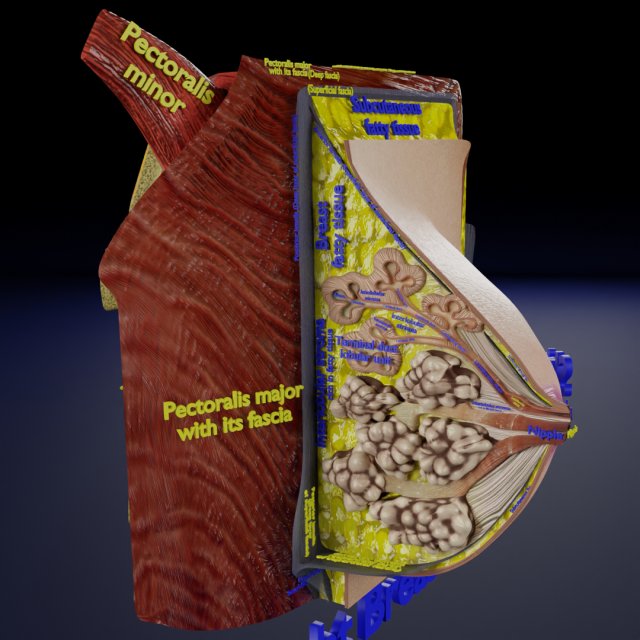

Breast anatomy histology detailed labelled precise to scale model 3D Модель

This is a 1:1 scaled model of right breast cut opened in sagittal plane to reveal its internal antomy and histology (schematic). The deeper parts and fascial layers are also depicted to give a very detailed approach to the model. The full layers starting from skin, nipple areola, till intercodtal muscles and ribs are also depicted.

The formats 3mf, ply, obj, fbx, USDZ,GLTZ & GLB with applied uv mapped textures have also been included in the downloads along with stl. Готовність до друку: Ні

breast mammary gland female chest wall anatomy human medical science reproductive genitalia muscle fascia milk nipple areola subcutaneous fatДо даного товару немає коментарів.